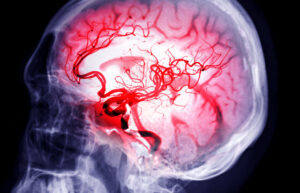

Stroke: Apa Berlaku Dalam Badan?

Stroke berlaku apabila aliran darah ke otak terhenti akibat saluran darah yang:

- tersumbat (Ischemic Stroke – 85% kes)

- pecah (Hemorrhagic Stroke – 15% kes)

Apabila darah tidak sampai ke otak, sel otak mula mati dalam beberapa minit. Bahagian badan yang dikawal oleh kawasan otak tersebut akan berhenti berfungsi.